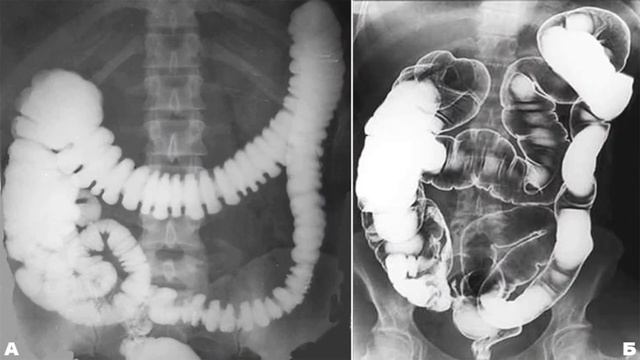

Нормы обзорной рентгенографии брюшной полости